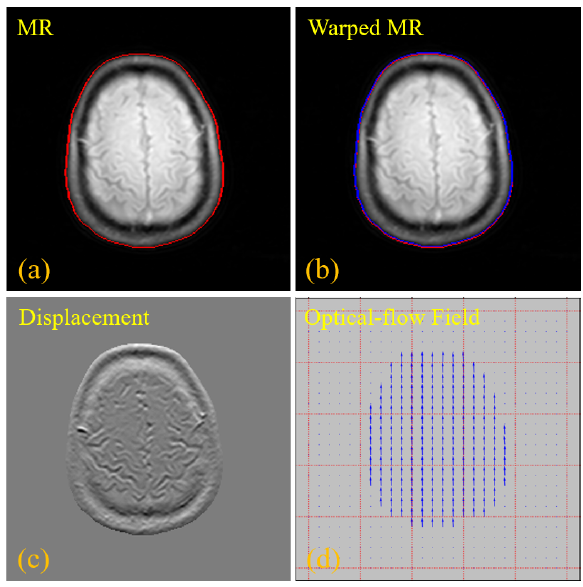

圖2 基于光流配準(zhǔn)的輪廓學(xué)習(xí)技術(shù),(a)原始輸入的MR 圖像,紅色曲線代表 MR圖像的輪廓,(b)配準(zhǔn)模塊校正后的 MR 圖像,藍(lán)色曲線表示配準(zhǔn)MR圖像的輪廓,(c)配置變換前后的MR圖像之間的像素強度差異,(d)稀疏光流場,顯示配準(zhǔn)預(yù)測網(wǎng)絡(luò)的水平和垂直方向偏移量

由于PET/MR兩種模態(tài)在紋理上存在顯著性差異,直接通過卷積學(xué)習(xí)這兩種模態(tài)之間的對齊映射關(guān)系非常困難。由此,團隊首先使用傳統(tǒng)的圖像腐蝕和膨脹技術(shù)來計算PET和MR圖像的主要輪廓,然后再基于這些輪廓信息來構(gòu)建光流的偏移量?;谳喞獙W(xué)習(xí)的方法不僅簡單有效,而且使得水平和垂直方向偏移量的學(xué)習(xí)也更加精準(zhǔn)。